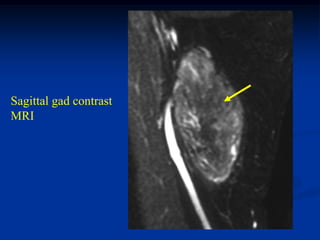

Case #1197

CLASSIC

37 year female with

hibernoma triceps m

Sagittal T-1 MRI

Axial T-1 MRI

Axial T-2 MRI

Axial gad

contrast MRI

Sagittal gad contrast

MRI

Surgical specimen showing tan color